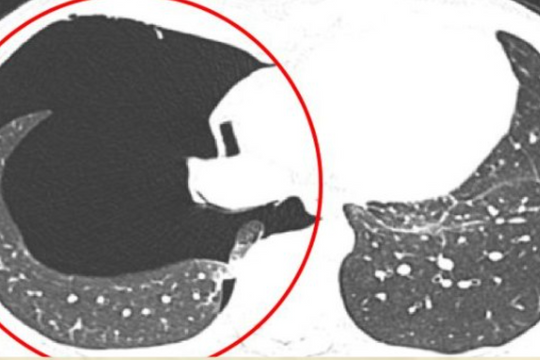

Nam thanh niên tràn khí màng phổi sau khi đẩy tạ quá sức

(CLO) Một chàng trai 25 tuổi, khỏe mạnh, không có tiền sử bệnh phổi đã phải nhập viện khẩn cấp sau khi đẩy tạ nặng tại phòng gym. Bác sĩ chẩn đoán anh bị tràn khí màng phổi tự phát, một biến chứng nguy hiểm có thể gây suy hô hấp nếu không được xử lý kịp thời.